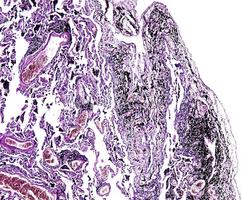

Histology

<smoker's lung/ healthy lung>